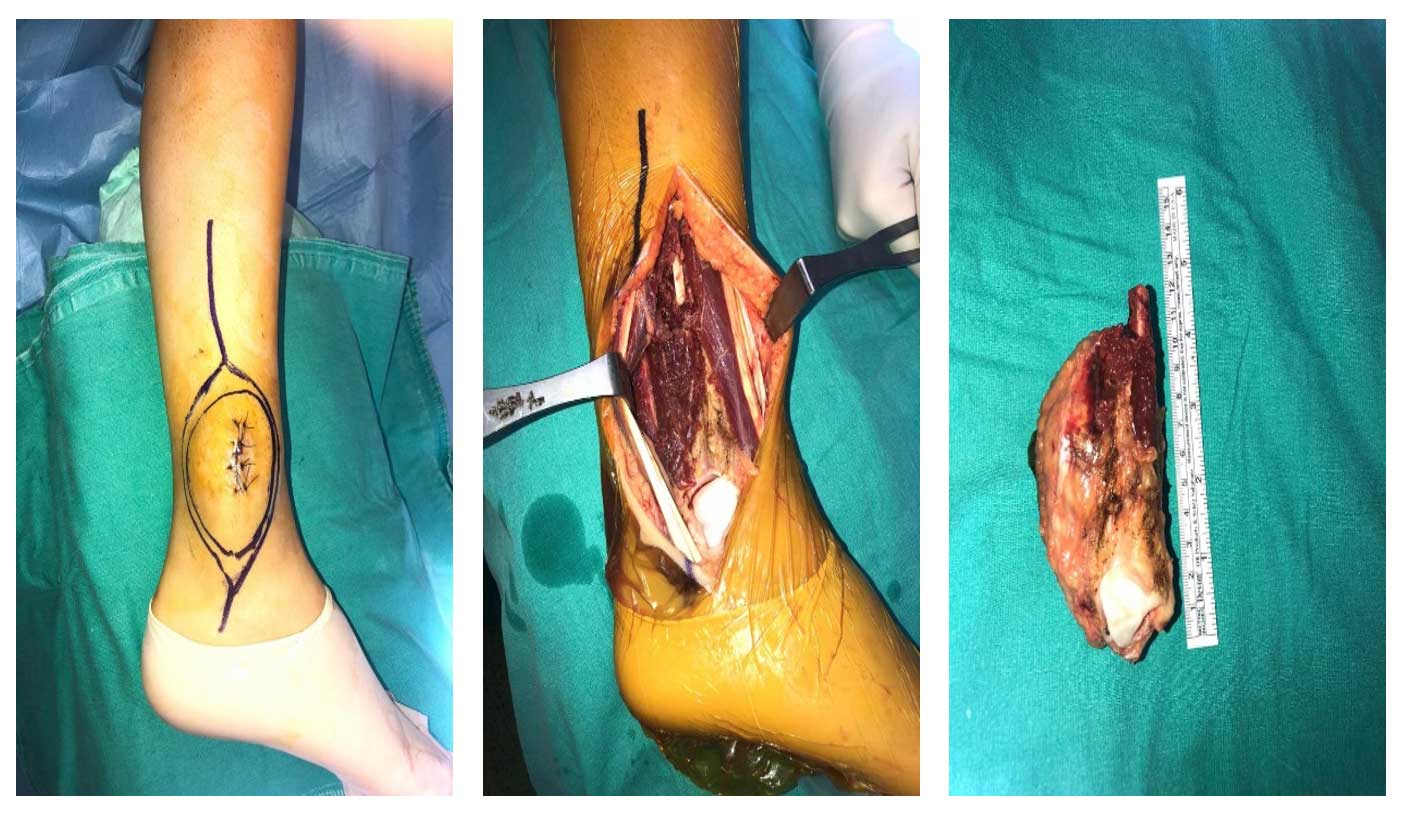

Ameliyat Esnası: İnsizyon hattı, rezeksiyon sonrası oluşan boşluk ve çıkarılan tümör kitlesi görülmekte.